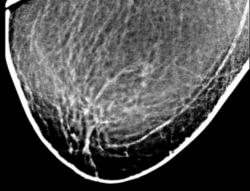

Цифровое стандартное маммографическое профилактическое исследование (проведено на цифровом маммографе МАДИС).

Протокол рентгенологического исследования. Общая скиалогическая картина фиксирует инволютивную железу в годы климакса. В верхнем наружном квадранте правой молочной железы в прямой и косой проекции (3) локально определяется некоторое подобие узлового образования средней интенсивности, неоднородной структуры, с нечеткими контурами.

После цифровой обработки изображения (1, 2) и выделения «навигатором» участка с патологическим образованием (4, 5) определяется локально участок перестройки структуры, на фоне которого определяется несколько макрокальцинатов. Аналогичный макрокальцинат располагается несколько ниже.

Заключение: Инволютивная молочная железа в годы климакса. Рентгенологических данных за уловое образование не обнаружено.